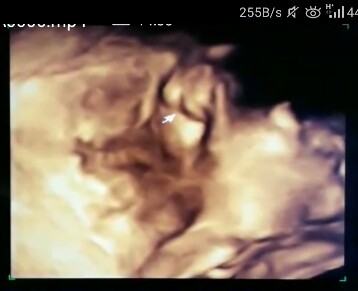

Ibu2 yang dah pernah scan, tau tak ni jantina apa? Perempuan ke laki? Private part baby di bhgian yg ada anak panah tu.

Mybe btul laa tu doc ckp, sbb nmpk cm beger.. π€